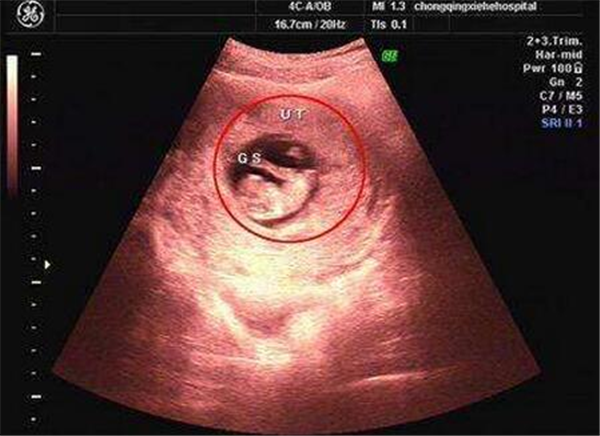

怀孕40天,做的第一次b超,医生说可能是双胞胎,但一个大一个小,有同样

怀孕40天b超能看到吗b超多久能看到孕囊

怀孕40天b超检测结果请大家看看本人万分焦急

怀孕40天去做b超检查能够查出哪些